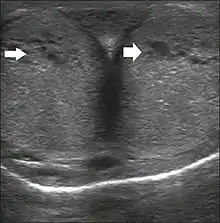

Penile ultrasonography with doppler can be used to examine the erect penis. Most cases of ED of organic causes are related to changes in blood flow in the corpora cavernosa, represented by occlusive artery disease (in which less blood is allowed to enter the penis), most often of atherosclerotic origin, or due to failure of the veno-occlusive mechanism (in which too much blood circulates back out of the penis). Before the Doppler sonogram, the penis should be examined in B mode, in order to identify possible tumors, fibrotic plaques, calcifications, or hematomas, and to evaluate the appearance of the cavernous arteries, which can be tortuous or atheromatous.[44]

Erection can be induced by injecting 10–20 µg of prostaglandin E1, with evaluations of the arterial flow every five minutes for 25–30 min (see image). The use of prostaglandin E1 is contraindicated in patients with predisposition to priapism (e.g., those with sickle cell anemia), anatomical deformity of the penis, or penile implants. Phentolamine (2 mg) is often added. Visual and tactile stimulation produces better results. Some authors recommend the use of sildenafil by mouth to replace the injectable drugs in cases of contraindications, although the efficacy of such medication is controversial.[44]

Before the injection of the chosen drug, the flow pattern is monophasic, with low systolic velocities and an absence of diastolic flow. After injection, systolic and diastolic peak velocities should increase, decreasing progressively with vein occlusion and becoming negative when the penis becomes rigid (see image below). The reference values vary across studies, ranging from > 25 cm/s to > 35 cm/s. Values above 35 cm/s indicate the absence of arterial disease, values below 25 cm/s indicate arterial insufficiency, and values of 25–35 cm/s are indeterminate because they are less specific (see image below). The data obtained should be correlated with the degree of erection observed. If the peak systolic velocities are normal, the final diastolic velocities should be evaluated, those above 5 cm/s being associated with venogenic ED.[44]